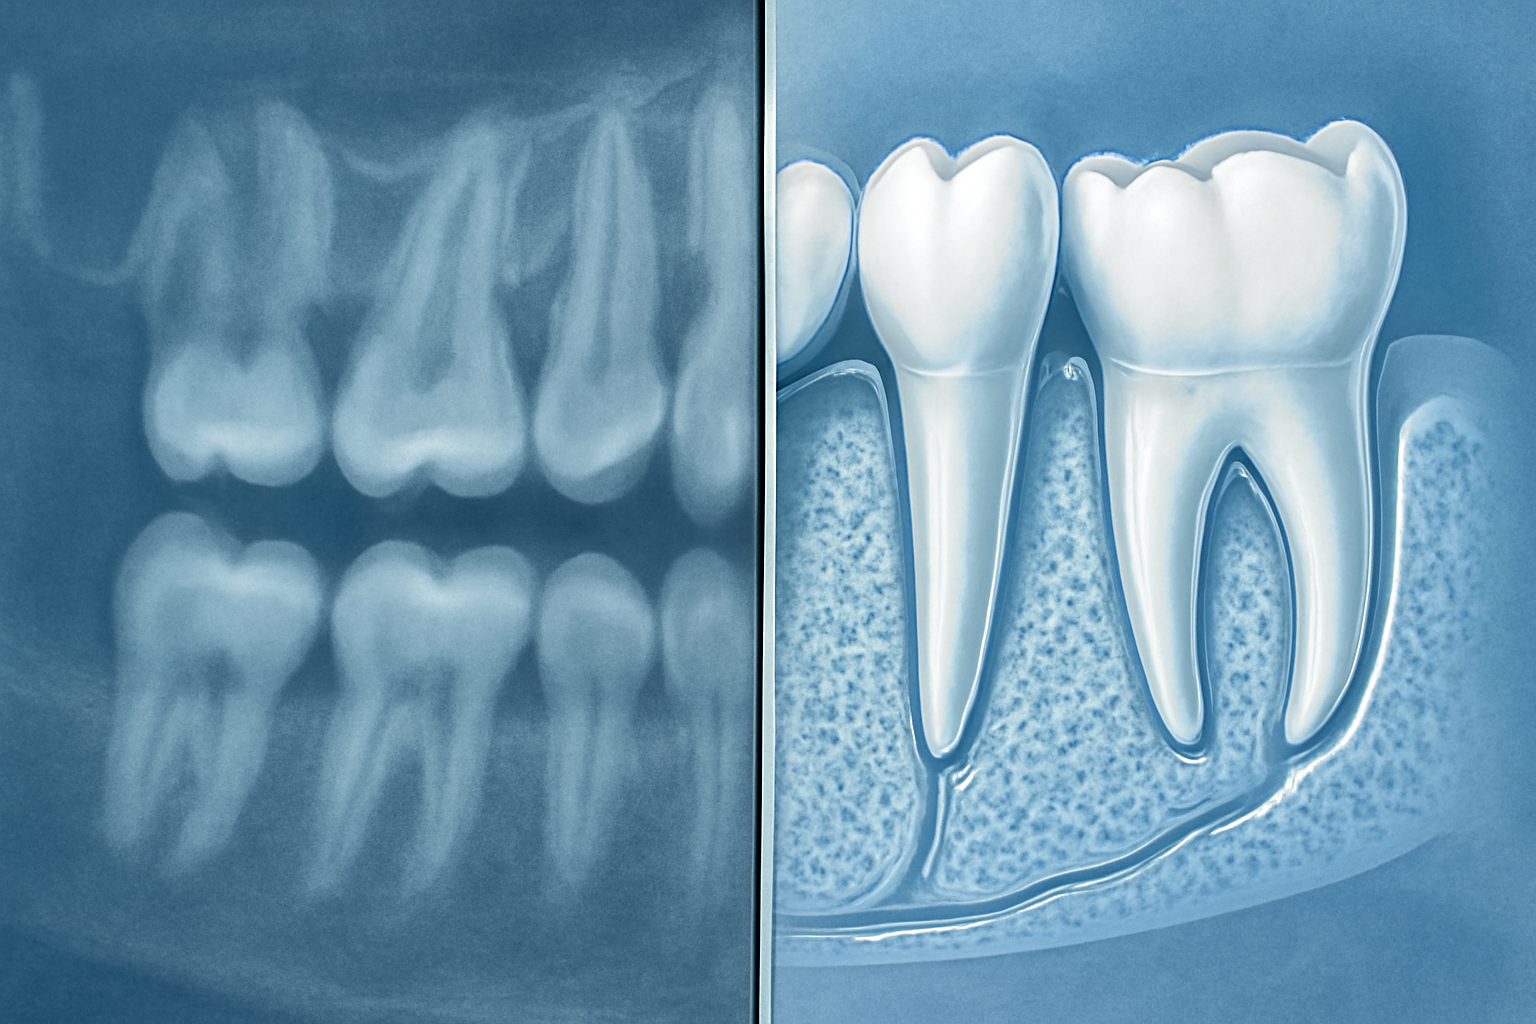

When it comes to dental implant planning, seeing the complete picture makes all the difference. Traditional 2D radiography, such as Orthopantomograms (OPGs), has long been the standard tool in dentistry. However, these flat images fail to capture the true complexity of oral anatomy, often leaving dentists partially blind to critical structures.

The limitations of 2D imaging are stark. These traditional radiographs compress three-dimensional structures into a single plane, causing overlapping images that obscure vital details. This flattening effect can hide important anatomical variations or pathologies that might affect implant success. Recent clinical research highlights a concerning reality: surgeons using only OPG imaging had to unexpectedly abort 7% of implant surgeries after beginning the procedure. The reason? They discovered insufficient bone quantity or couldn't achieve primary stability – issues that remained hidden on 2D scans but would have been obvious with 3D imaging.

Cone Beam Computed Tomography (CBCT) addresses these shortcomings by providing comprehensive volumetric data. Unlike traditional radiography, CBCT captures the entire region of interest in three dimensions, allowing dentists to examine potential implant sites from every angle. This third dimension transforms implant planning from educated guesswork into precise surgical mapping.

The ability to view oral structures in axial, coronal, and sagittal planes gives dentists unprecedented insight into the patient's anatomy. This multi-dimensional perspective reveals the exact height, width, and depth of available bone – measurements that significantly impact implant success rates. Additionally, CBCT enables accurate evaluation of bone density, helping clinicians select appropriate implant designs and surgical protocols based on bone quality.